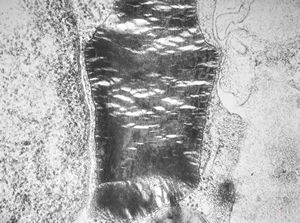

M,17y. | Alport syndrome - split and laminated basement membranes

F,14y. | Alport syndrome - split and laminated, thick/thin basement membranes